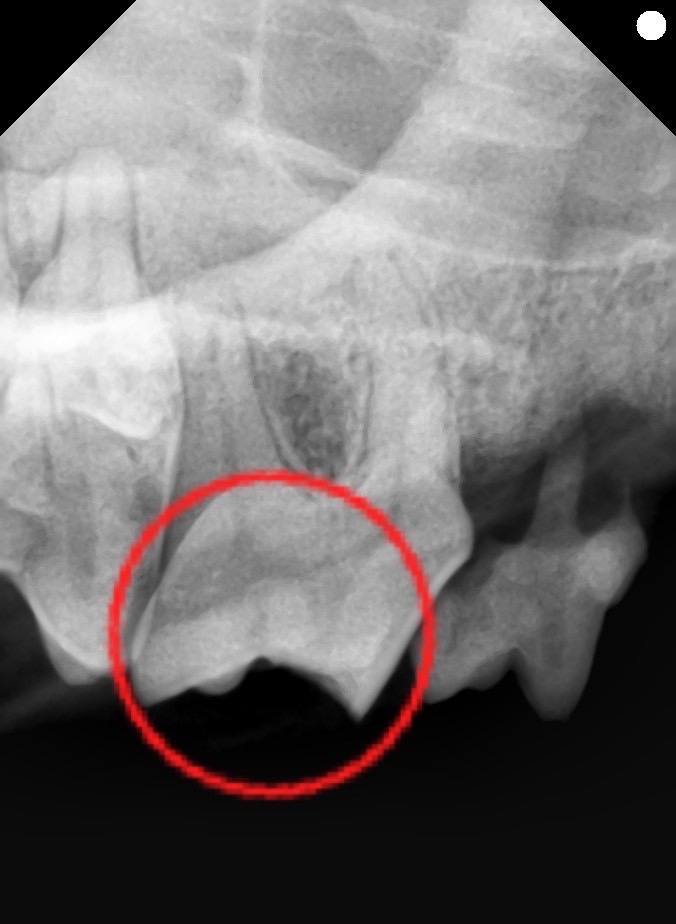

全身麻酔下で歯科検診・歯科レントゲン検査を行ない、

右第4前臼歯破折(歯肉縁下まで)

・象牙質露出

・乳歯遺残

・欠損歯

・歯肉炎軽度

が認められました。